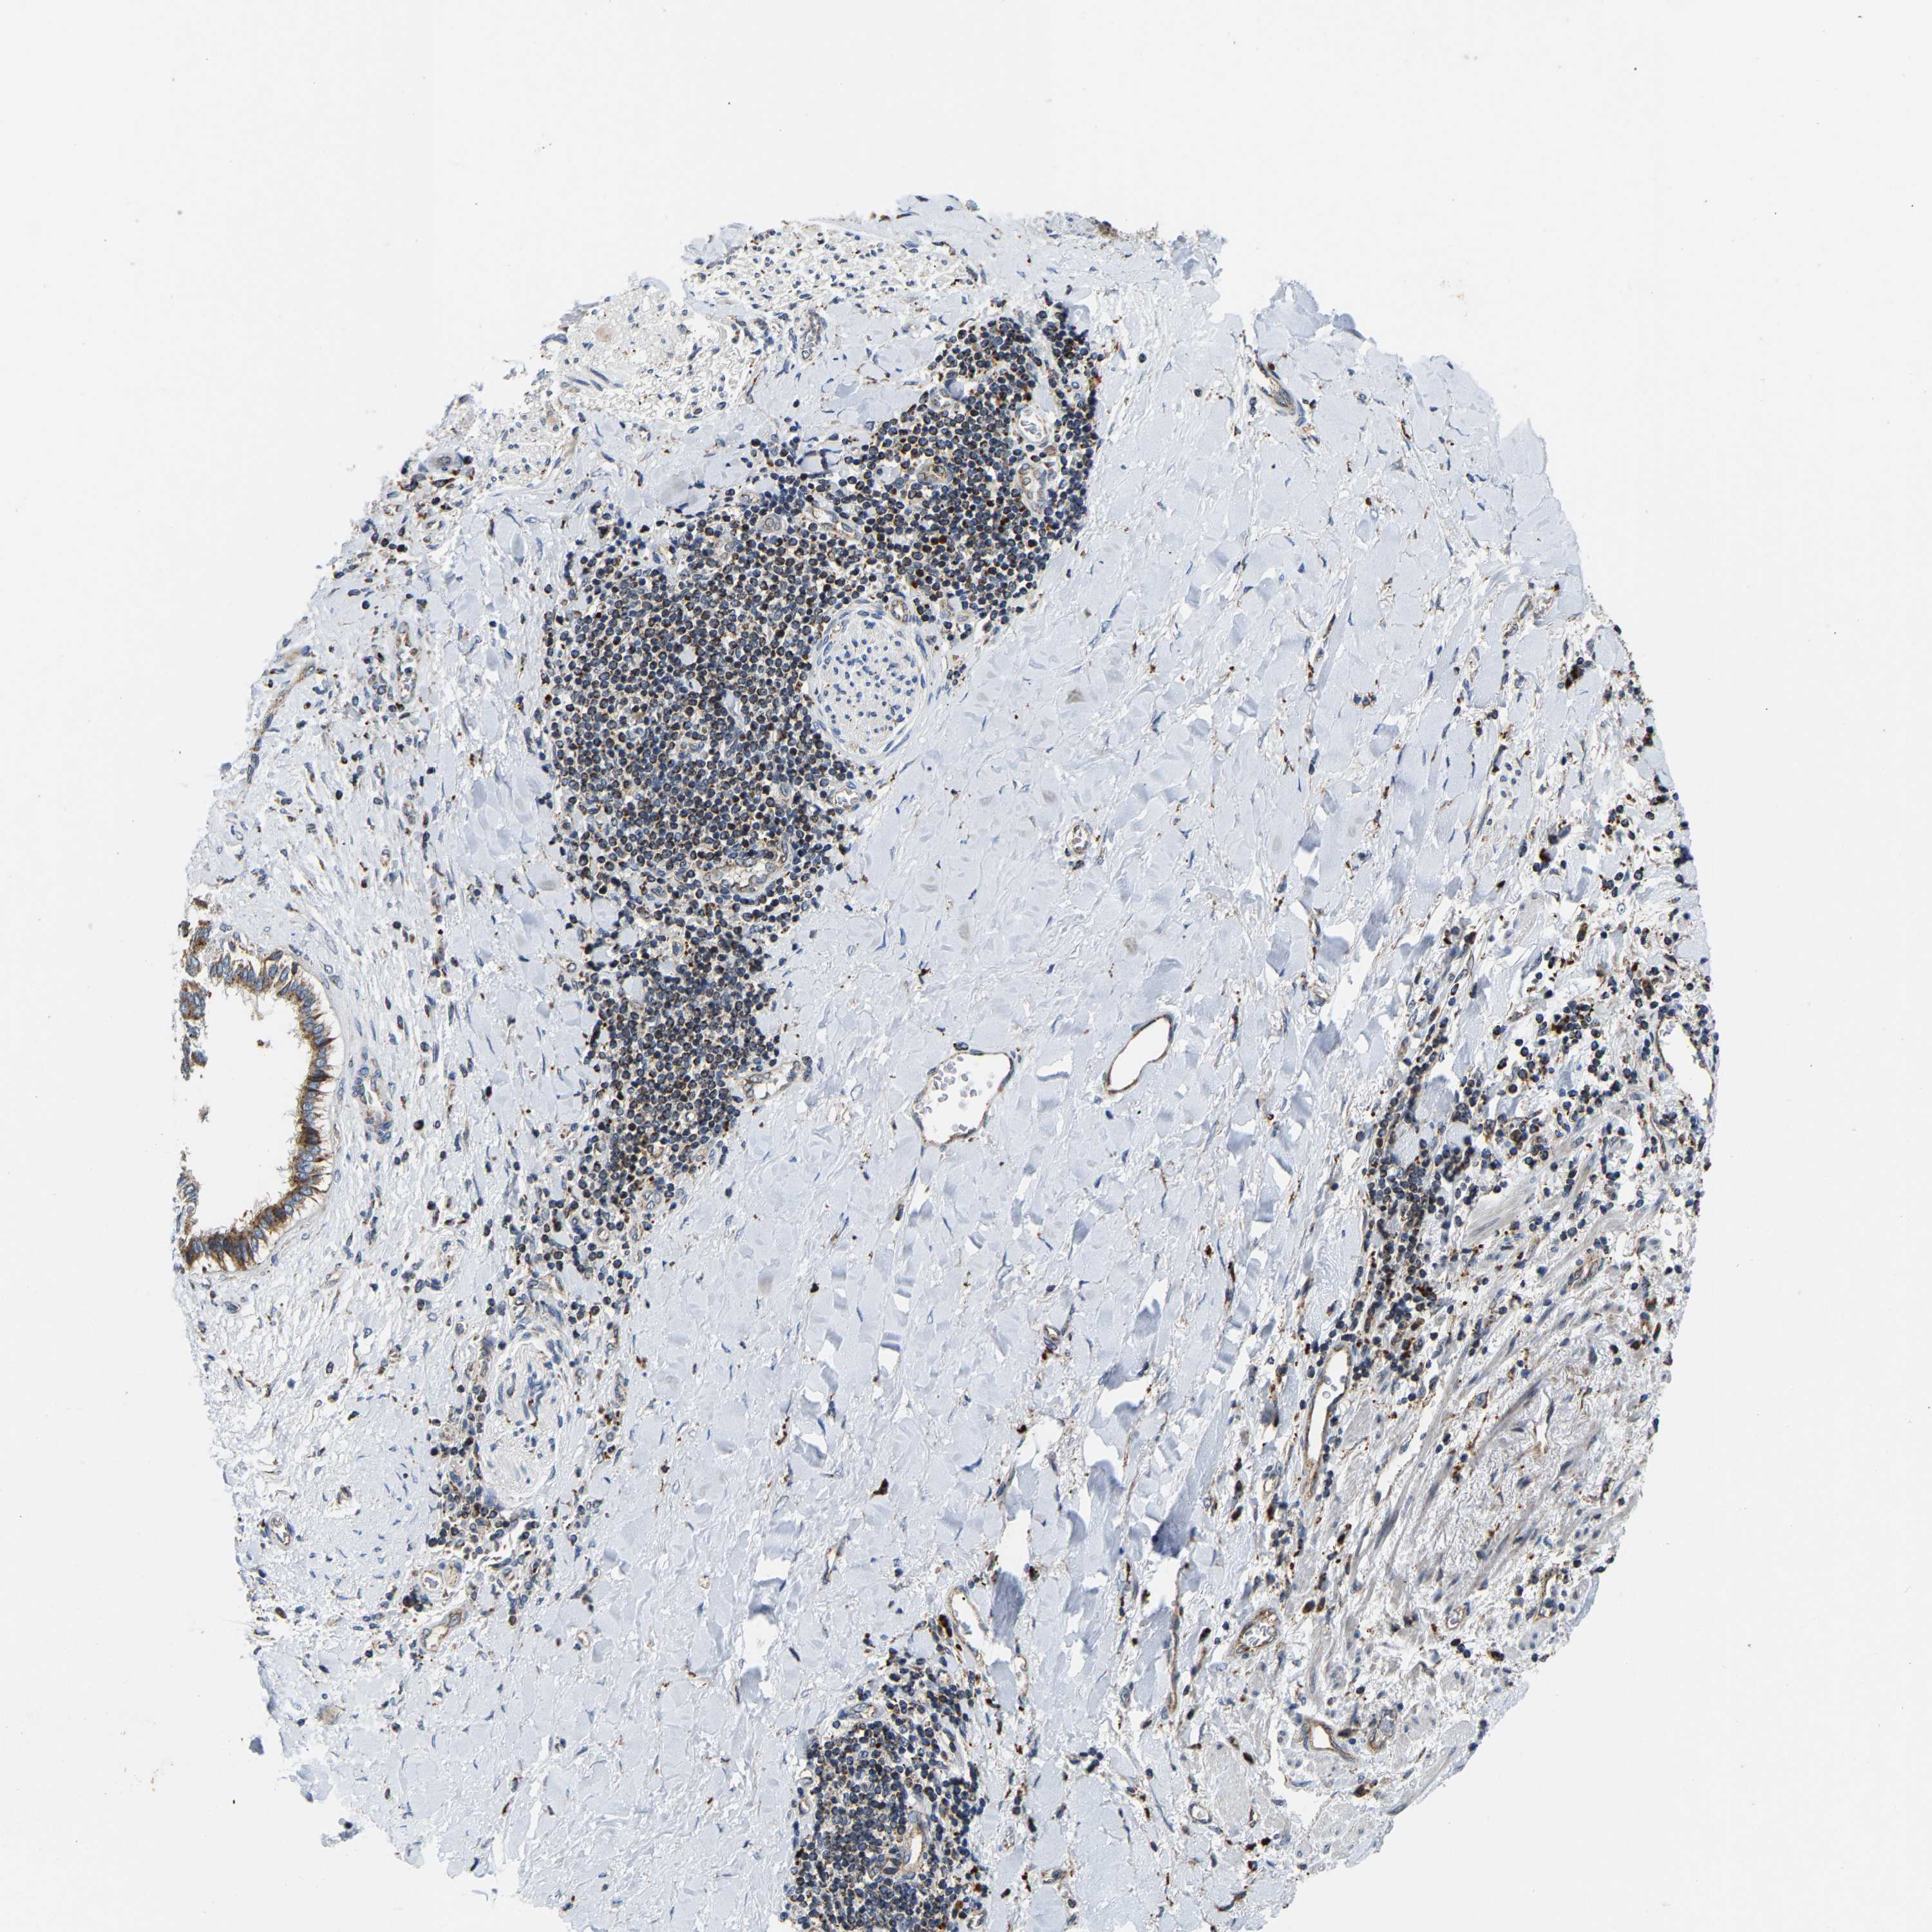

LIVER CANCER - Protein expressioni

A mouse-over function shows sample information and annotation data. Click on an image to view it in a full screen mode. Samples can be filtered based on level of antibody staining by selecting one or several of the following categories: high, medium, low and not detected. The assay and annotation is described here.

Antibody stainingi

Antibody staining in the annotated cell types in the current human tissue is reported as not detected, low, medium, or high, based on conventional immunohistochemistry profiling in selected tissues. This score is based on the combination of the staining intensity and fraction of stained cells.

Each image is clickable and will lead to virtual microscopy that enables deeper exploration of all samples and also displays staining intensity scores, fraction scores and subcellular localization as well as patient and tissue information for each sample.

Antibody HPA020266

Antibody HPA020268

Staining

High

Medium

Low

Not detected

Intensity

Strong

Moderate

Weak

Negative

Quantity

>75%

75%-25%

<25%

None

Location

Nuclear

Cytoplasmic/membranous

Cytoplasmic/membranous,nuclear

Cholangiocarcinoma

Carcinoma, Hepatocellular, NOS